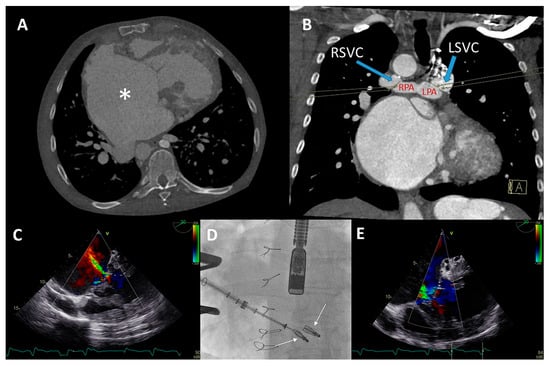

Figure 6.

(A,B) Computed tomography (CT) scan of the thoracic cavity with the anatomical position of the dilated functional mono-atrium (asterisk) against the right thoracic wall (panel A) and bidirectional bilateral Glenn shunt (panel B) (LPA = left pulmonary artery, RPA = right pulmonary artery, LSVC = left superior vena cava, RSVC = right superior vena cava). (C) Pre-procedural transesophageal echocardiography (TEE) which visualized severe common atrioventricular (AV) valve regurgitation. (D) Anteroposterior fluoroscopic view of the two XTW MitraClips positioned in the AV valve. At the same time, it is appreciated that the delivery system is positioned through the fifth intercostal space after a right mini-lateral thoracotomy. (E) Moderate AV regurgitation after the hybrid procedure visualized with TEE.

Conventional surgical AV valve replacement or repair was considered extremely high risk due to the anatomical relation between the atrium and the thoracic wall, the extensive coronary fistulae, and the reduced ventricular function. Percutaneous AV valve replacement or repair was deemed non-feasible by the transvenous route due to interruption of the IVC with azygos continuation and sharp angulation into the mono-atrium (for a transfemoral approach). Furthermore, a transjugular approach was not feasible because of the bilateral Glenn connection. Therefore, it was decided that a hybrid procedure under general anesthesia with direct atrial access using a MitraClip delivery system (Abbott, IL, USA) was the best strategy.

The congenital cardiothoracic surgeon performed a right (mini) lateral thoracotomy in the fifth intercostal space to expose the giant mono-atrium. A double-purse string suture was placed and an incision was made to create an opening using a Safari wire for guidance and stability. The interventional cardiologist then placed two XTW clips under TEE guidance (Figure 6D), resulting in reduction in AV valve regurgitation to grade II (Figure 6E). Post-procedural TEE showed grade II regurgitation with stable position of the clips. No peri-procedural complications occurred. The patient could be discharged with adequate heart failure medication with an improvement in NYHA functional class (II). Unfortunately, the patient died after 9 months due to progressive ventricular dysfunction, worsening of the AV valve regurgitation, and heart-failure-related multi-organ dysfunction (NYHA functional class IV at the latest admission).